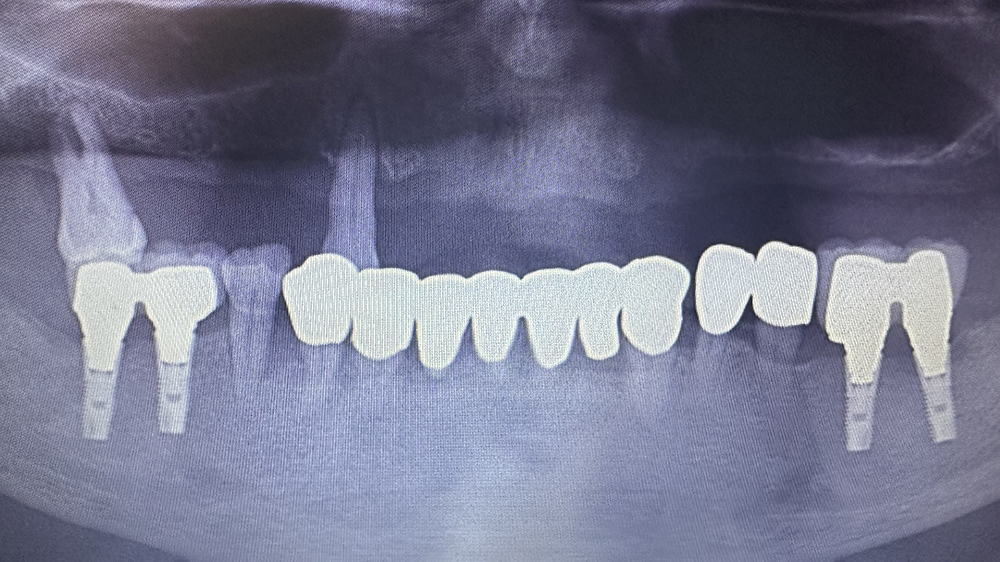

症例3

Before

After

MHさん、84歳女性

非喫煙者

治療の期間・回数:約6か月

​治療の価格:約2,200,000円

治療内容:当院では平成5年から上あごの「オールオンX」を行っていますが、この方は最も古い患者さんです。

すでに21年経過しています。右下の歯が折れたため、12年前にオステムインプラントを1本追加しました。